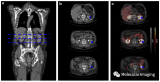

发现恶性肿瘤立即做手术? 先进行PET/CT全身显像检查

PET/CT全身显像不仅能了解原发肿瘤局部情况、周围淋巴结有无转移,而且可对全身其他器官情况进行评估,监测肿瘤是否发生远处转移及转移的程度,有助于临床医生根据患者肿瘤分期制定个性化治疗方案。 2022-08-05 PET/CT